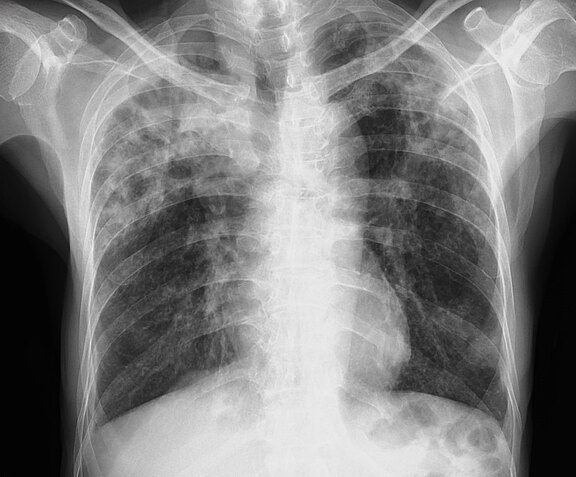

Eine gesunde Lunge ist entscheidend für Lebensqualität und Leistungsfähigkeit. In der Klinik für Pneumologie am Klinikum Bayreuth behandeln wir alle Erkrankungen der Lunge, der Atemwege und des Rippenfells – von Asthma, COPD und Lungenentzündung bis zu Lungenfibrose, Lungenhochdruck oder Lungenkrebs.